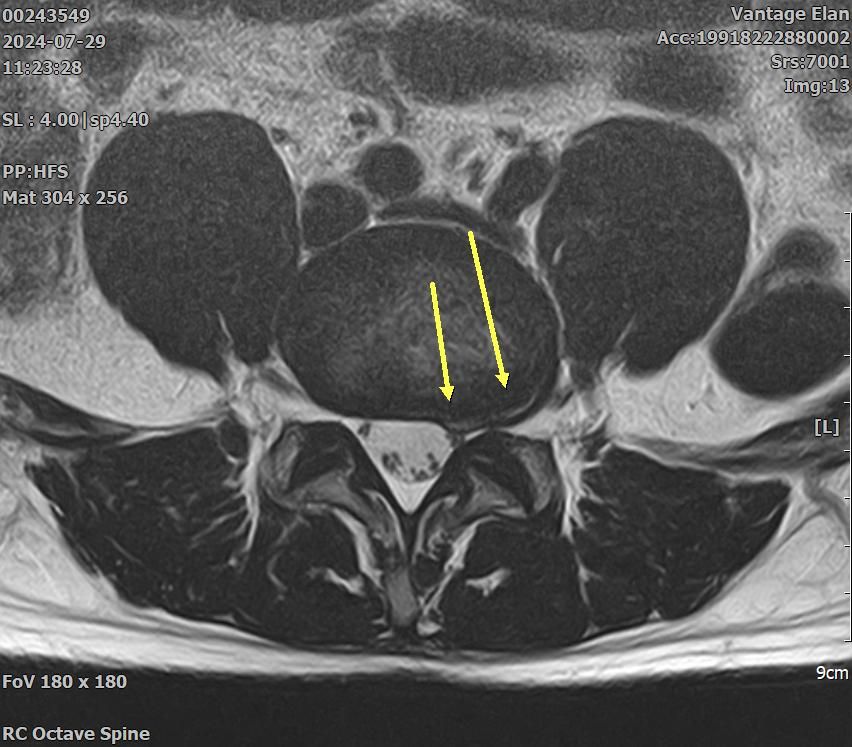

21년도와 24년도 각각 찍은 L spine 사진입니다.

2024년 영상